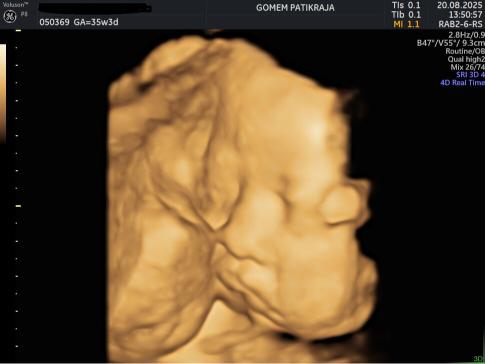

Perkembangan Janin 35 Minggu:

Pada minggu ke-35, berat janin terus bertambah dan gerakan masih terasa walaupun tidak seaktif sebelumnya. Ruang di dalam rahim semakin sempit. Ibu mungkin mulai sering merasakan perut kencang atau kontraksi palsu. Ini normal selama tidak teratur dan tidak semakin kuat. Persiapan persalinan sebaiknya mulai dilakukan pada minggu ini.

Gambaran Hasil USG Janin 35 Minggu